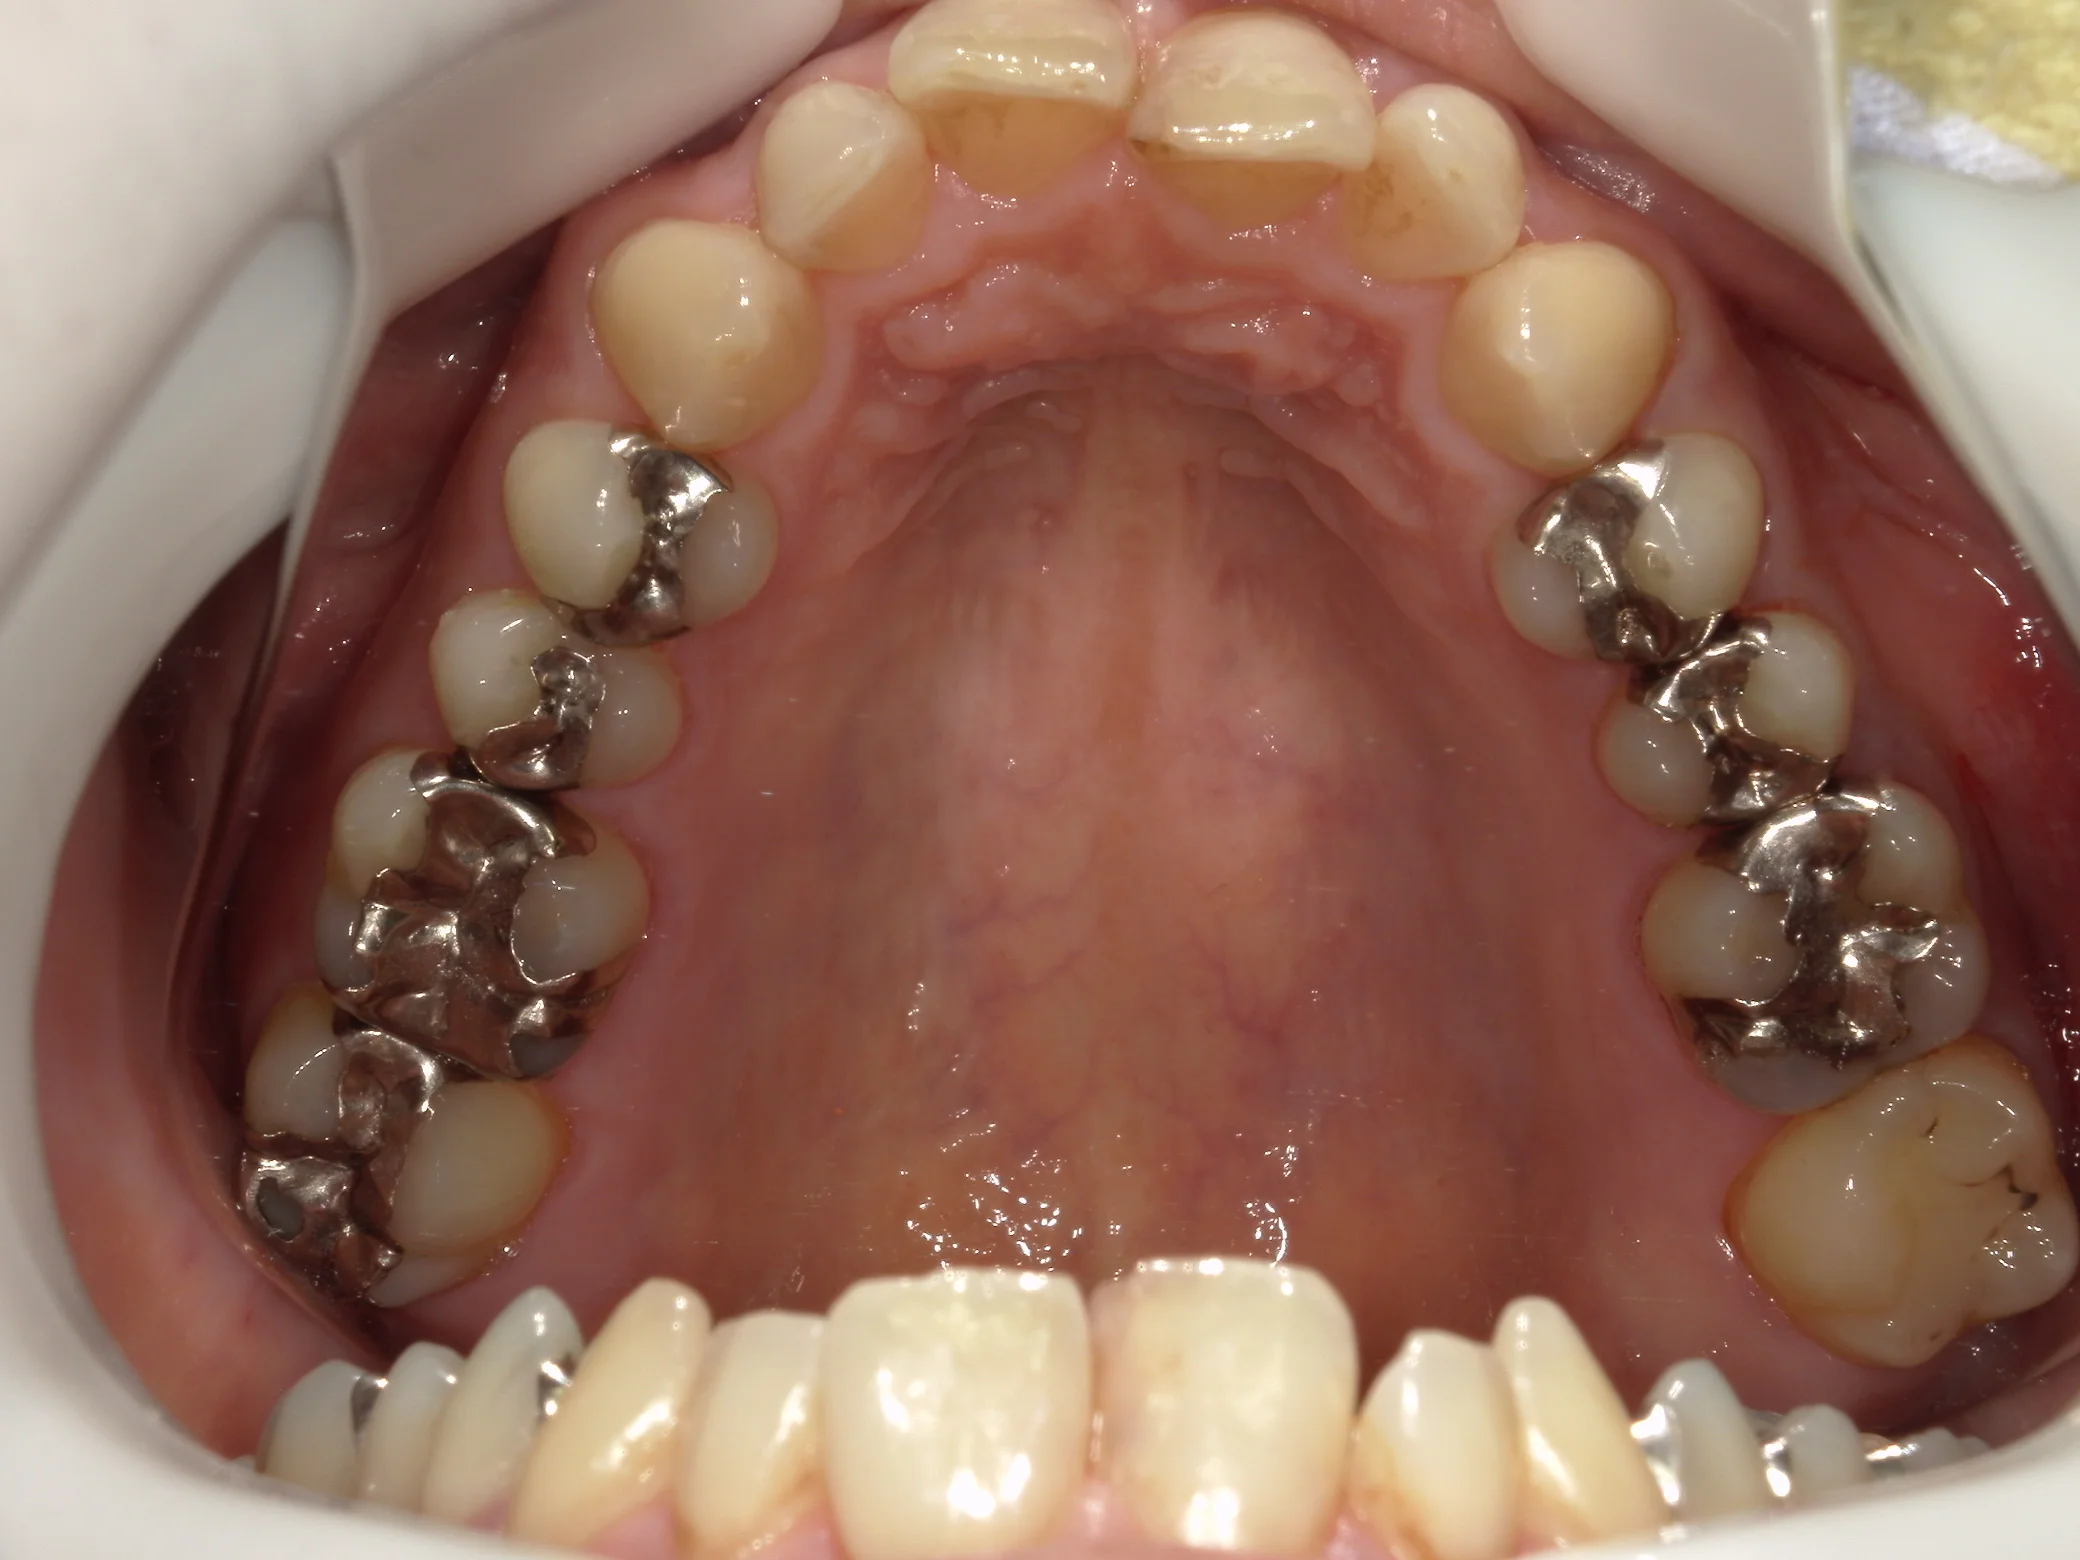

そして詰め終わったのがこちらです。

基本的には噛み合わせの調整は最小になるように行うべきですが、少し多めに調整することになってしまいました。

そして、別アングルからの写真がこちらです。

こちらが、術前。

こちらが術後。

随分と自然な感じに仕上げることが出来たと思います!